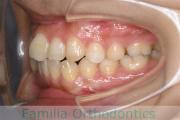

No.22V-185

- 主な症状:

- 上下顎前突

- 年齢:

- 28歳

- 性別:

- 女性

- 抜歯部位

- 上:

- 44

- 下:

- 448

- 主な使用装置:

- FEA 022

- 治療にかかった費用:

- 90万円

口元に力が入ってしまうのを治したいということで来院されました。上の側切歯が小さいのですが、しっかり前歯を後退させたいということで。上下左右から小臼歯を抜歯してマルチブラケット法にて治療を行い、移動後に側切歯の補綴(かぶせ物)処置をしました。

約2年半、30回程度の通院が必要でした。

側切歯が小さい場合、上下の歯のバランスが悪いため、最終段階で人工的な補綴物が必要になります。補綴物には破損や脱離のリスクがあります。